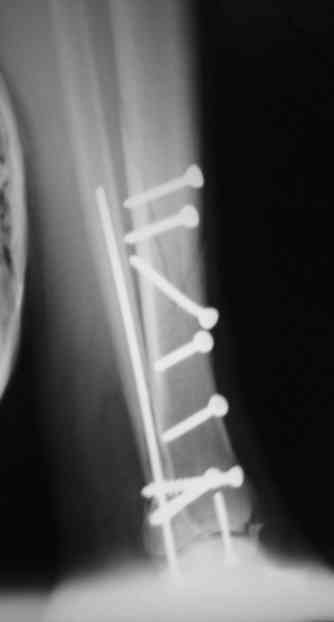

Сегодня прооперировали. Длительность 4-50. Начали как и говорил сверху вниз линейным разрезом - фиксация задне-латерального отломка к проксимальному 2мя винтами, затем "прилепили" к ним передне-медиальный (пришлось повозиться - была интерпозиция и довольно "сложный" винт) - к проксимальному 1 винтом и к задне-латеральному 1 винтом.Кстати на фото видно - у передне-медиального отломка еще осколок в области сустава, несколько смят. Далее началось веселье - второй доступ - задне-наружный к латеральной лодыжке и заднему краю, но оказалось, что задний край больше задне-медиальный (по снимкам было непонятно). Плюс к этому репозиция его мягко говоря сложновата (больной на спине, стол низкий и не поднимается). В общем выставили, фискировали 2мя винтами, на ЭОПе вроде стал, только верх отошел. Латеральную лодыжку заведующий решил интрамедуллярно (не хотел еще винты толкать), сначала 3мм спицей - нестабильно, затем 4мм стержень (не помню по автору) - ОК (кстати в месте перелома мелкая крошка - дефект до 5х7 мм по кортикалу). Ну медиальная лодыжка стандартно - третий разрез - винт 3,5 мм. Визуально все стабильно. На Р-контроле - видна небольшая ступенька заднего края по одному из контуров.

Фото с операции

Нельзя ли попросить снимки именно голеностопного сустава. Представлены снимки голени в нижней трети.Сустав фактичеси не виден.

Александр, если вы имеете в виду послеоперационные Р-граммы - то это все что есть. А сустав виден достаточно, чтобы оценить то что есть

Вы представили снимок голени в нижней трети. На сустав луч упал косо, это искажает.

Есть подозрение, что имеется ступенька заднего края, внутренняя лодыжка оттопырена. Взаимоотношения в суставе важнее, чем точная репзиция диафиза.

> Есть подозрение, что имеется ступенька заднего края, внутренняя лодыжка оттопырена. Взаимоотношения в суставе важнее,

> чем точная репозиция диафиза.

Ступенька заднего края и в самом деле вроде есть, но видна по одному из контуров - я о этом писал выше. А лодыжка должна стоять на месте - ставили-то открыто - да и на снимках положение ее правильное.

В боковой проекции - диастаз, 0,5-1мм.